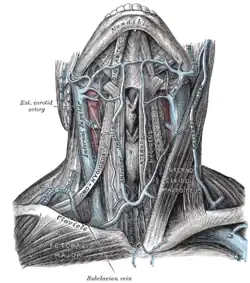

Veias do pescoço, vistas de frente

Veias do pescoço, vistas de frente -